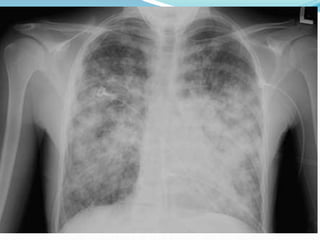

 New CXR infiltrates

CXR - non specific infiltrates